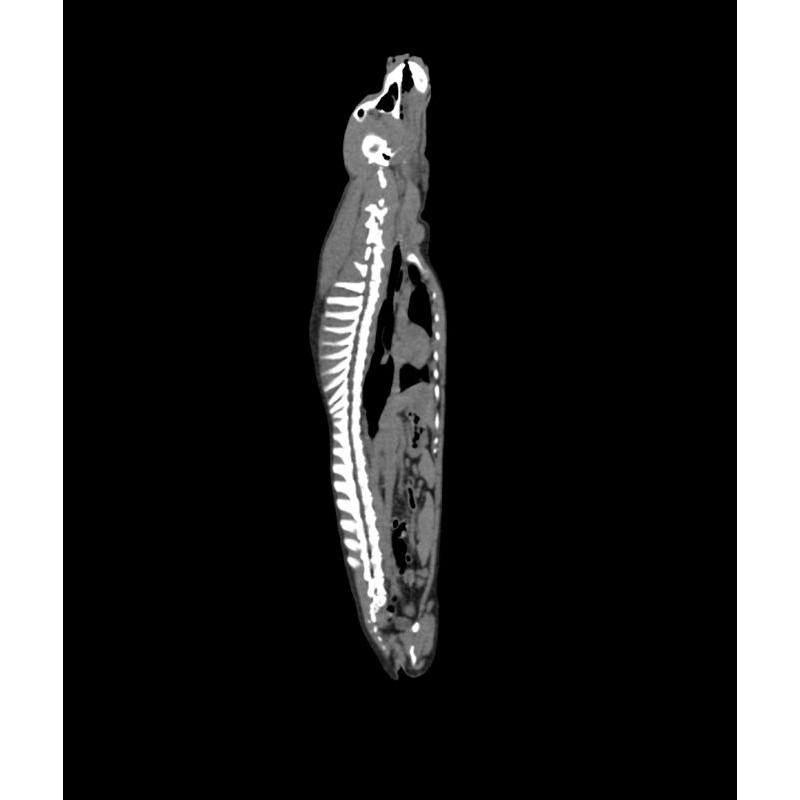

Fantom zagotavlja realistično simulacijo psa brez kontrastnega sredstva. Kosti in mehka tkiva so prikazana verodostojno z realističnimi vrednostmi CT za vsa tkiva pri 120 kVp napetosti cevi v CT. Zračni prostori so zapolnjeni s celuloznim polimernim kompozitom s približno -80 Hounsfieldovimi enotami.

Če se bo fantom uporabljal predvsem pri drugih napetostih cevi (npr. 100 kVp), se lahko po potrebi ustrezno prilagodi kalibracija vrednosti CT ? Fantom zagotavlja tudi realistične kontraste tkiv pri rentgenskem slikanju.

Velikost: 26x15x80 cm